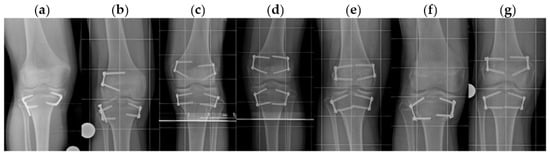

2.2. Indication, Operative Technique, and Applied Implants

2.3. Implants Applied for Epiphysiodesis